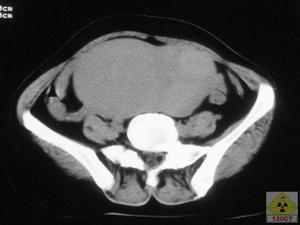

3.CT掃描 具有良性腫瘤的各種CT征,多位於眶後部,圓形或類圓形,邊界清楚均質注射陽性對比劑後中度增強,可見眶腔擴大。腫瘤中可有多個鈣斑,術後切開標本證實了有鈣化區。發生於眶尖者可引起眶上裂擴大。